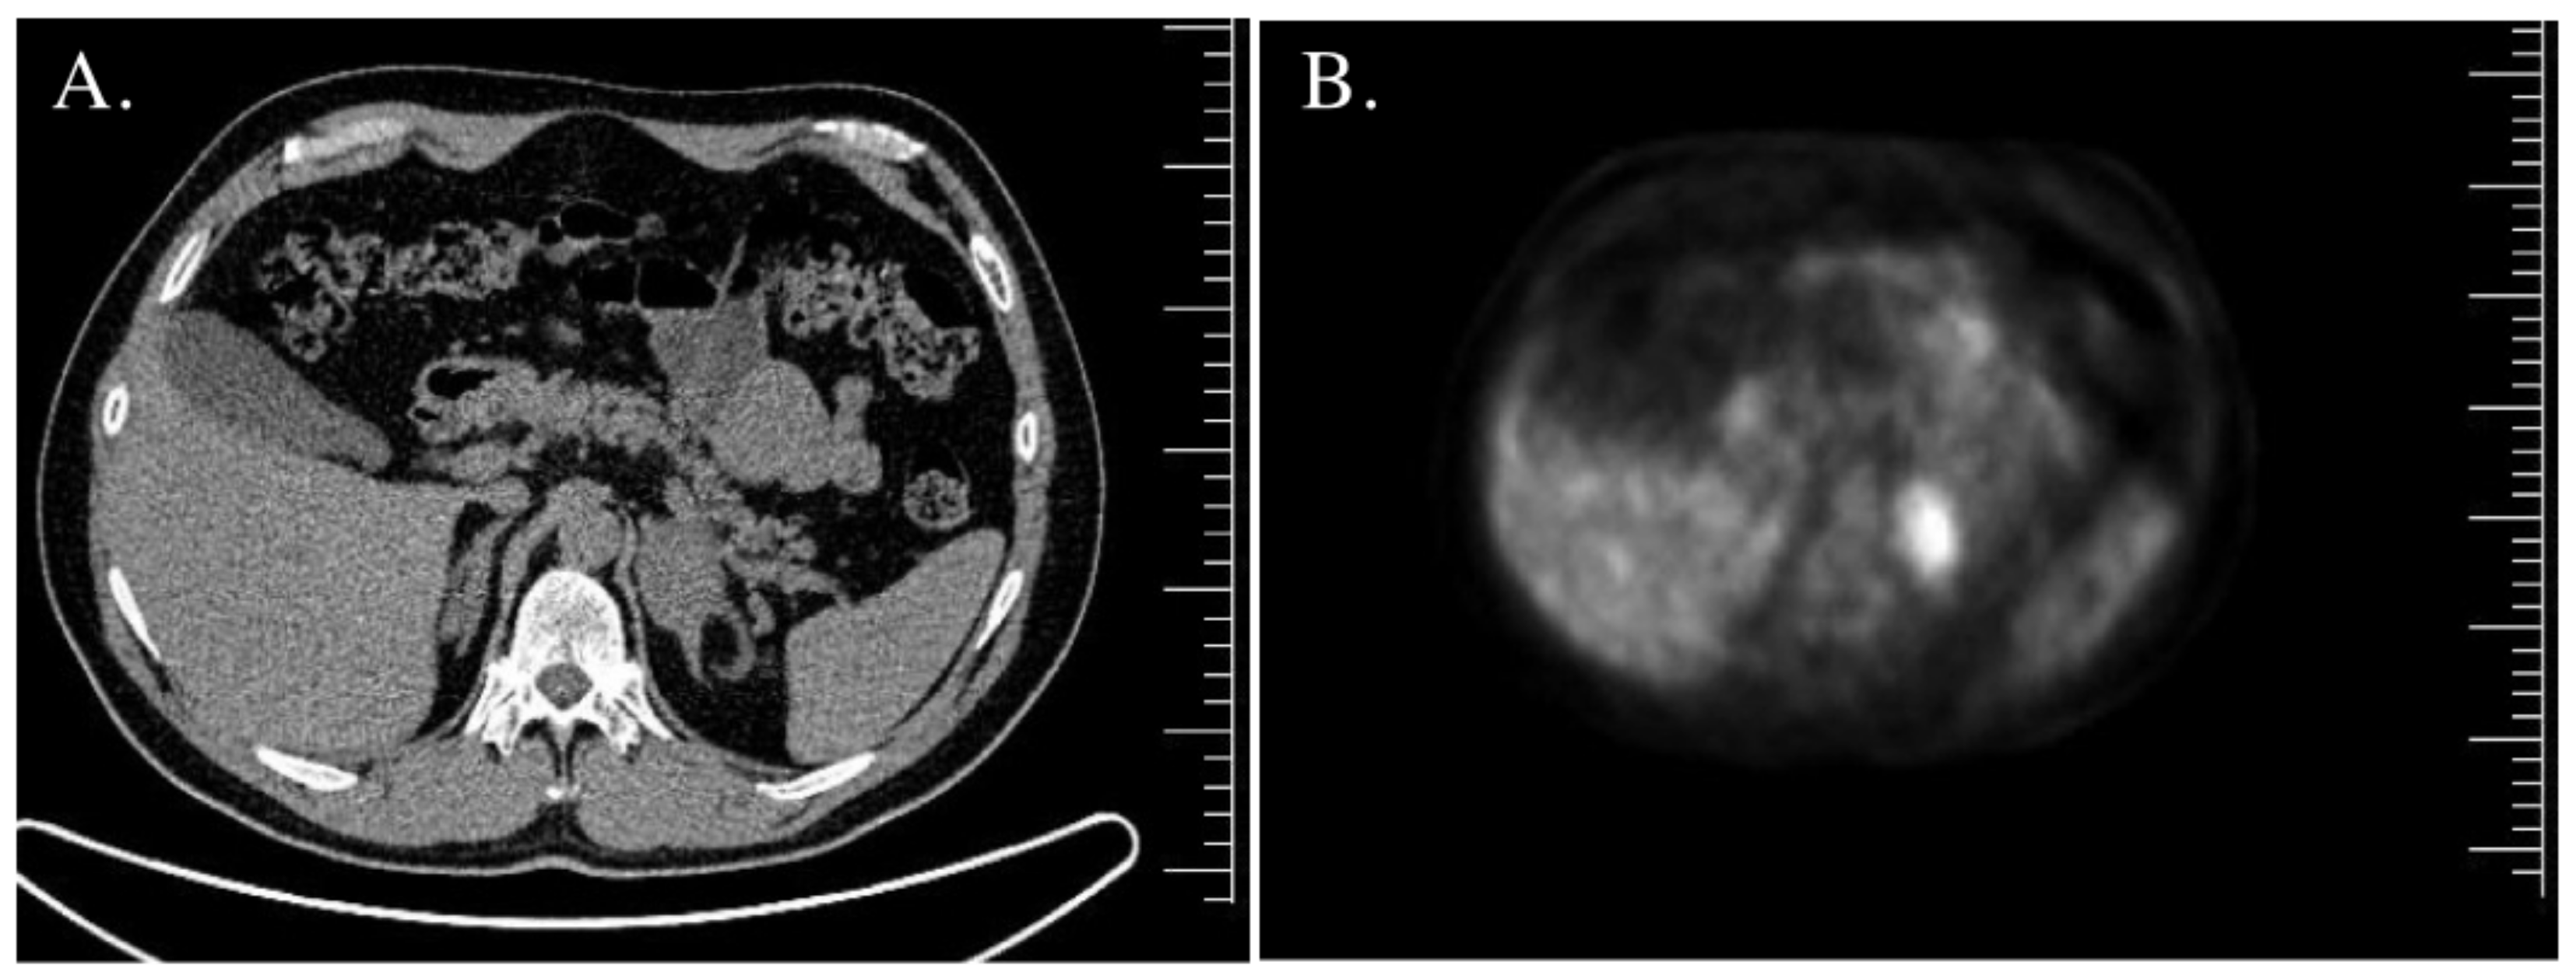

| Adrenal gland imaging | Normal. | CT—bilateral adrenal tumors, right—45 mm × 30 mm × 37 mm (20 HU), left—18 mm × 14 mm × 11 mm (30 HU). | MRI—right adrenal tumor, 85 mm × 57 mm × 70 mm; inhomogeneous, without signal loss in out-of-phase. Left adrenal hypertrophy. | MRI—left adrenal tumor, 44 mm × 38 mm; inhomogeneous, borderline signal loss in out-of-phase; 18FDG PET/CT—increased uptake. Right adrenal in normal size. |

| Adrenal gland imaging | CT—right adrenal tumor 20 mm, 26 HU; MRI—signal loss in out-of-phase. Left adrenal normal in size. | CT—bilateral adrenal hypertrophy. | MRI—left adrenal tumor 44 mm—borderline signal loss in out-of-phase; right adrenal adenoma 16 mm × 10 mm × 7 mm; 18FDG PET/CT—increased uptake (SUVmax 7.6) in the left adrenal tumor. | CT—bilateral adrenal hypertrophy (left adrenal 42 mm × 30 mm, right adrenal 55 mm × 35 mm). |